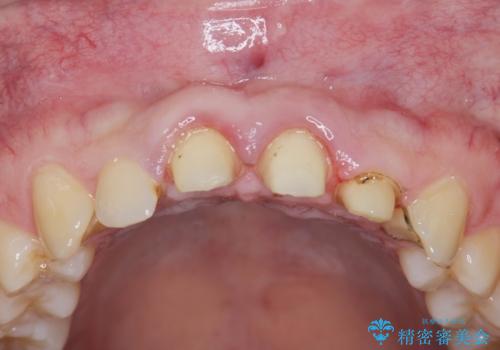

- 「前歯の見た目、歯ぐきの腫れを改善したい。」と希望され来院されました。

前歯には接着性の維持装置や、中途半端な形の連結クラウンが装着され、清掃性が悪く歯ぐきの腫れや、歯ぐきの形態の不揃いが認められました。

ただ、白いオールセラミッククラウンを製作・装着するのではなく、将来にわたり安定した状況を獲得するため、歯周外科を行い歯ぐきと周囲の歯槽骨の形態を整えていきます。